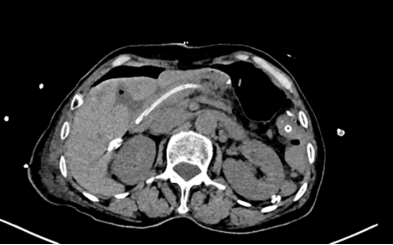

胰头部肿瘤紧挨肠系膜上静脉,治疗刻不容缓

完善检查检验结果后,患者被确诊为胰头癌合并梗阻性黄疸,李中和副院长组织肝胆外科、影像医学部、肿瘤中心、药学部、临床营养科等科室专家进行多学科会诊,制定治疗方案。专家们认为,肿瘤已经压迫胆管,导致患者黄疸,出现了严重的肝功能损害,幸运的是肿瘤并未发生远处转移,肿瘤边界与肠系膜上静脉将近180度毗邻,仍属于可切除情况,若再晚几个月就医,肿瘤侵犯到静脉,可能会彻底丧失手术机会,现在要争取根治性切除,但必须分步完成,将风险降至最低。最终,专家们讨论决定先行超声引导下经皮肝胆管穿刺置管引流术,待患者肝功能好转后,再行全腹腔镜下胰十二指肠切除术。

李坚主任表示,检查提示患者肿瘤虽然没有发生远端转移,但肿瘤跟肠系膜上静脉挨得很近,手术既要将肿瘤切干净又不能搞破血管,这无疑又增加了手术难度,因此术中还要做好血管联合切除重建的预案。